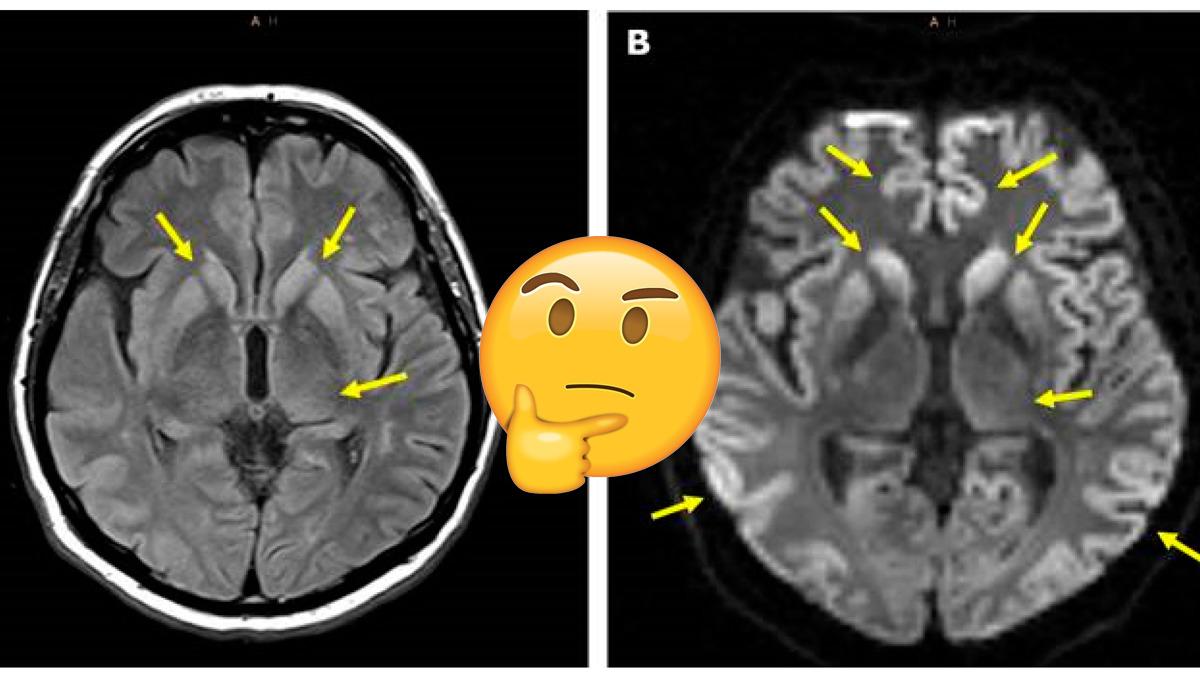

Öte yandan bu rahatsızlığa, beyindeki prionlar yani anormal proteinler sebep oluyor. Bu proteinler de dokularda ne yazık ki geri döndürülmesi imkânsız hasarları beraberinde getiriyor.

Aynı zamanda beynindeki çoğu nöronun düzgün çalışmamasına ve ölmesine sebep olan sünger benzeri delikleri yaratıyor.